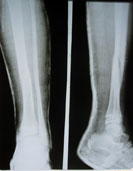

Хочу описать мою и моего мужа состояние, особенно его. который так трепетно относится к своему первенцу, в которой души не чает. Наша девочка очень подвижная, даже очень, оно понятно-познаёт мир. Мы уже свыклись с её постоянными царапинами, ушибами, ссадинами. Но 6 июня случилось супер вон выходящее... Во время прогулок в детском саду, качаясь на качелях, она с неё упала и сломала ногу. Как я узнала от воспитателя, сразу-же вызвали скорую помощь и отвезли в детскую больницу. Мне позвонили и через пол часа я уже была там. Она была бледная, слабенькая, перепуганная, я как понимаю в шоке. В травмпункте ей наложили гипс на всю ногу и сказали: не беспокойтесь, всё будет хорошо. В поликлинике Вам снимут через месяц. По квынзиу пару дней дочка встала потихоньку ходить наступая на гипс. К концу снятия, она разбила его в тряпочку. В назначенный срок пришли к хирургу в поликлинику, когда сняли гипс я была в шоке. Её ножка стала колесом, стала видимо короче, а снаружи колена, какая то кость выпирала кверху. Моему возмущению не было предела, хирург молоденький парнишка, увидев что, что то не то мямлил: ну я не знаю, Вам надо обратиться в травматологическое отделение. Схватив в охапку дочку, мы с мужем не медля сразу же повезли, где накладывали гипс. В приёмном покое на наши просьбы, мольбы-СРОЧНО! Вышел солидный мужчина, посмотрел ребёнка, рентгеновские снимки и сказал:"Ну что Вы волнуетесь, кости стоят не плохо, для ребёнка это нормально. Пройдёт время и всё исправится."

Прошла неделя, всё как было, так и осталось даже хуже. Мы с мужем измеряли каждый день сантиметром, опять добились консультации. Ответ один и тот же: ну что Вы волнуетесь, всё в порядке. Но мы же видим стопа вывернута наружу, а голень короче. Появившаяся вверху кость возле колена никуда не уходит,мы поняли что в Гос.структуре нас никто не поймёт. Наслышаны с детства, так как живём в Павлодаре, о волшебствах Онипко. Чуть ли не одновременно задали вопрос друг другу, а почему сразу не обратились? В виду его занятости попали к нему на консультацию только лишь на 3-й день, подключили и родственников и всех знакомых. Осмотрев ребёнка, он сказал:" Врачи сделали всё грамотно, и сделали всё квалифицированно и правильно."

А на вопрос мужа, так почему так всё произошло? Он спокойно ответил:такое бывает. Муж опять: кто виноват-врачи, я хочу призвать их к ответственности. А Онипко: никто, так сложился случай. Это бывает редко, но встречается. У Вас глубокий косой перелом, учитывая что девочка у Вас гиперактивная, при нагрузке и ходьбе в гипсе смещение могло произойти. Но если произошло, значит кто то виноват. А муж искал знакомых адвокатов, чтобы наказать. Онипко ещё раз повторил: врачи здесь не причём и показал пальцем вверх-всё от всевышнего и многие вещи от нас не зависит. Защищая своих врачей, а он там работал 13 лет зав.отделением, убеждал нас, что может произойти само исправление с возрастом. Но на наш вопрос: Вы убеждены на 100%, долго думая со вздохом, если честно на 100-нет. И начал философствовать, что даже советский аэрофлот не даёт гарантию. У меня создалось впечатление, что у них у врачей, особенно которые работали вместе и долгие годы знали друг друга будут оправдывать, защищать и т.д. Так что нам делать? Думайте. Мы с мужем не спали ровно двое суток. На 3-й день пришли и сказали, оперируйте. И что и как это будет, объясните. "Учитывая что ребёнок через тоненькие спицы прокольчики, без швов, слегка послабив уже сросшуюся неправильно б/б кость устранив создавшуюся укорочение, скрученость кости и подвывих м/б. Уверен, что Ваш ребёнок уже через неделю будет бегать в аппарате." Поверили, потому что от него исходила такая уверенность!!! На следующий день сдали анализы и 13 июля нас прооперировали. Всё получилось на что мы надеялись, дочка на 2-й стала ходить на костылях наступая на прооперированную ножку. На 5-й день начались манипуляции с аппаратом, она вообще никак на них не реагировала и с каждым днём была всё активнее. Когда забывали напомнить ей про костыли, она ходила без них смешно прихрамывая. После рентгеновского снимка в четверг, Н.Н. ей ещё что то подкрутил и отправил нас домой в г. Иртышск. Заходила гл.медсестра, перевязочная и подробно объяснили, как делать перевязки. Убедили что всё пройдёт спокойно,а если уж 1 на 1000, то срочно на вертолёте и на площадку клиники (шучу). У нас наконец то наступило успокоение и уверенность, что всё будет хорошо. Всем спасибо.